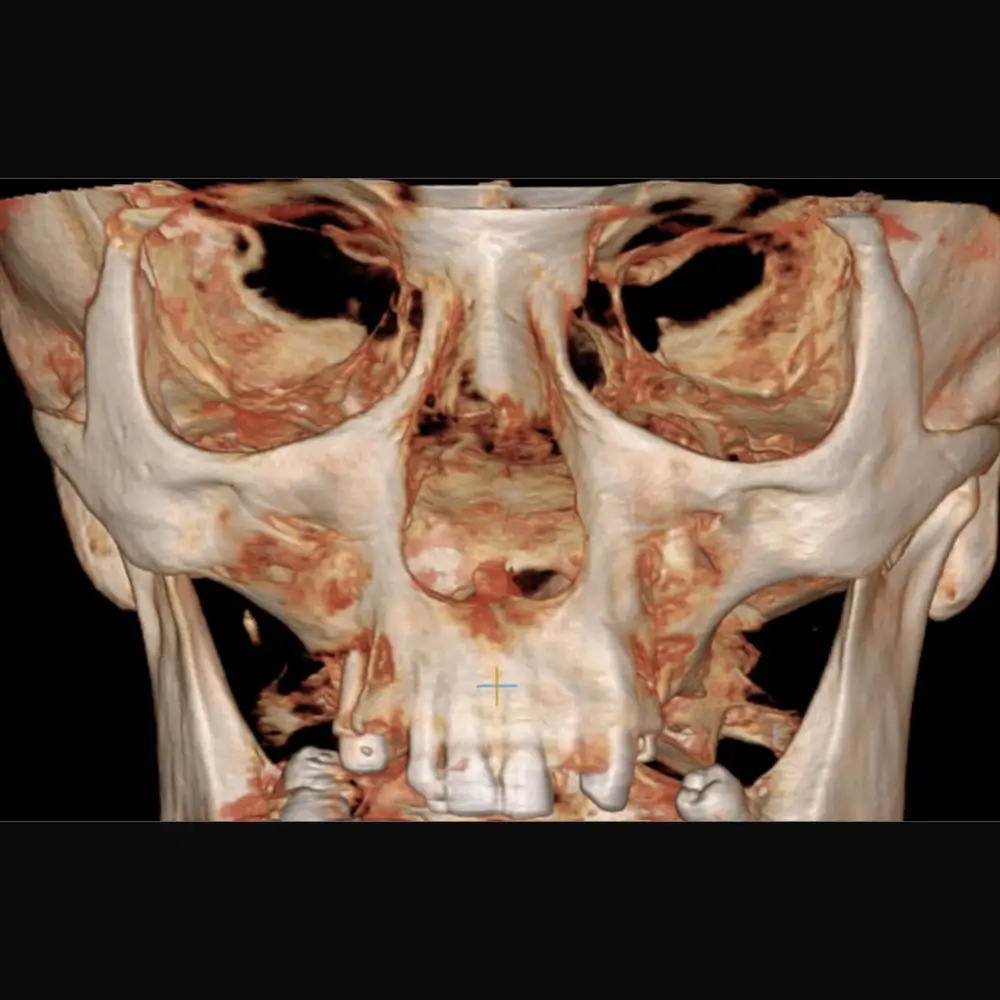

Tomografia computerizată cu fascicul conic (CBCT) este o tehnologie de vârf utilizată în imagistica dentară, oferind imagini tridimensionale extrem de clare și detaliate. Edenta Radiologie și Imagistică Medicală utilizează CBCT-ul (tomografia dentară) pentru a examina structurile dentare și maxilare, oferind reconstructii 3D volumetrice complete și complexe care vin în ajutorul medicului stomatolog.

Tehnologia CBCT utilizează un fascicul conic de raze X pentru a captura imagini detaliate ale structurilor anatomice, esențiale pentru planificarea intervențiilor chirurgicale sau pentru diagnosticarea afecțiunilor dentare complexe. Aceste imagini 3D sunt fundamentale în evaluarea implanturilor dentare, a tratamentelor ortodontice și a altor proceduri și intervenții care necesită o precizie ridicată.

Utilizarea tomografiilor computerizate (CBCT) pentru a obține imagini tridimensionale ale maxilarelor și dinților sunt fundamentale în intervențiile chirurgicale de precizie și în tratamentele ortodontice, oferind medicilor stomatologi o vedere completă și detaliată asupra structurii dentare.

Imaginile obținute prin tehnologia CBCT sunt de o calitate superioară, permițând medicilor să identifice cu exactitate patologia existentă și să planifice un tratament eficient. Siguranta, confortul și grija pentru pacient împreuna cu tehnologia avansată pot deveni rețeta unui tratament reușit.